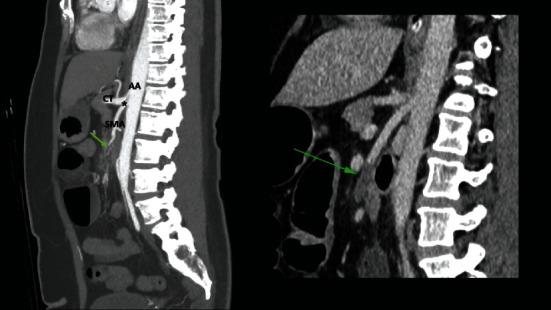

腹腔镜下松解治疗与腹腔干-肠系膜上动脉相关的正中弓状韧带压迫综合征

Laparoscopic Release for Median Arcuate Ligament Compression Syndrome Associated with a Celiac-Mesenteric Trunk.

The median arcuate ligament compression syndrome is a rare entity that occurs in 2 per 100,000 unselected individuals. We present a case where the median arcuate ligament compression syndrome was associated with an equally uncommon anatomic variation-a celiac-mesenteric trunk, which occurs in 0.42-2.7% of unselected individuals. We could find no prior report of a celiac-mesenteric trunk being associated with the median arcuate ligament compression syndrome. This report also adds to the literature to show that a laparoscopic approach to median arcuate ligament release is feasible.

正中弓状韧带压迫综合征是一种罕见疾病,在每10万名未经筛选的个体中约有2人发病。我们报告了一例正中弓状韧带压迫综合征合并同样罕见的解剖变异——腹腔干-肠系膜上动脉共干的病例,该解剖变异在未经筛选的个体中发生率为0.42%-2.7%。我们未发现此前有腹腔干-肠系膜上动脉共干与正中弓状韧带压迫综合征相关的报道。本报告还补充了文献资料,表明腹腔镜下正中弓状韧带松解术是可行的。